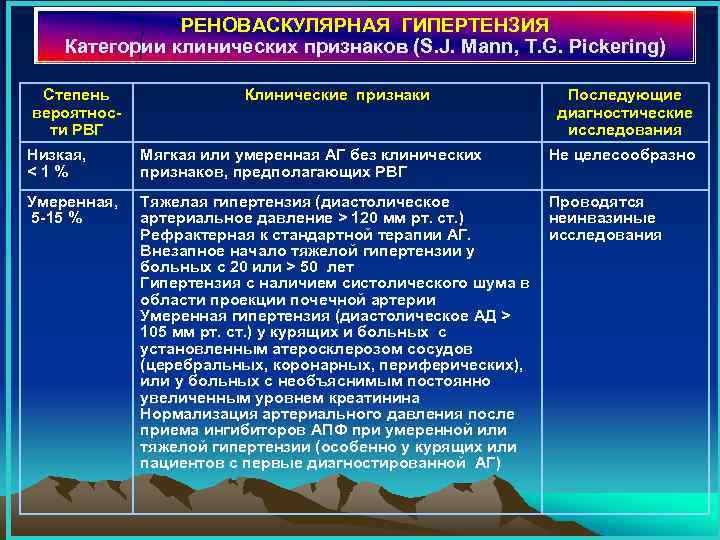

РЕНОВАСКУЛЯРНАЯ ГИПЕРТЕНЗИЯ Категории клинических признаков (S. J. Mann, T. G. Pickering) Степень вероятности РВГ Клинические признаки Последующие диагностические исследования Низкая, < 1 % Мягкая или умеренная АГ без клинических признаков, предполагающих РВГ Не целесообразно Умеренная, 5 -15 % Тяжелая гипертензия (диастолическое Проводятся артериальное давление > 120 мм рт. ст. ) неинвазиные Рефрактерная к стандартной терапии АГ. исследования Внезапное начало тяжелой гипертензии у больных с 20 или > 50 лет Гипертензия с наличием систолического шума в области проекции почечной артерии Умеренная гипертензия (диастолическое АД > 105 мм рт. ст. ) у курящих и больных с установленным атеросклерозом сосудов (церебральных, коронарных, периферических), или у больных с необъяснимым постоянно увеличенным уровнем креатинина Нормализация артериального давления после приема ингибиторов АПФ при умеренной или тяжелой гипертензии (особенно у курящих или пациентов с первые диагностированной АГ)

РЕНОВАСКУЛЯРНАЯ ГИПЕРТЕНЗИЯ Категории клинических признаков (S. J. Mann, T. G. Pickering) Степень вероятности РВГ Клинические признаки Последующие диагностические исследования Низкая, < 1 % Мягкая или умеренная АГ без клинических признаков, предполагающих РВГ Не целесообразно Умеренная, 5 -15 % Тяжелая гипертензия (диастолическое Проводятся артериальное давление > 120 мм рт. ст. ) неинвазиные Рефрактерная к стандартной терапии АГ. исследования Внезапное начало тяжелой гипертензии у больных с 20 или > 50 лет Гипертензия с наличием систолического шума в области проекции почечной артерии Умеренная гипертензия (диастолическое АД > 105 мм рт. ст. ) у курящих и больных с установленным атеросклерозом сосудов (церебральных, коронарных, периферических), или у больных с необъяснимым постоянно увеличенным уровнем креатинина Нормализация артериального давления после приема ингибиторов АПФ при умеренной или тяжелой гипертензии (особенно у курящих или пациентов с первые диагностированной АГ)